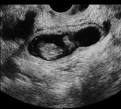

- Palpación rectal: Un productor puede utilizar palpación rectal entre los 40 y los 60 días luego de la inseminación para detectar el feto en el útero, otras estructuras asociadas con la preñez y la presencia de un cuerpo lúteo en el ovario.

- Crecimiento del feto: El crecimiento del feto se acentúa durante las últimas semanas de la preñez, por lo tanto este método es un poco tardío para la detección de la preñez.